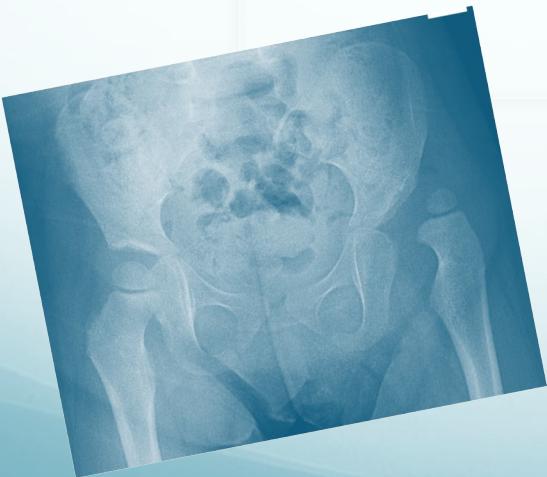

After 6 months:

- Clearly shows dislocation

- Size of femoral head ossific center

- Horizontal line through the tri-radiate cartilage

Position Assessment:

- Dislocated: Above the horizontal line

- Normal: Below the horizontal line